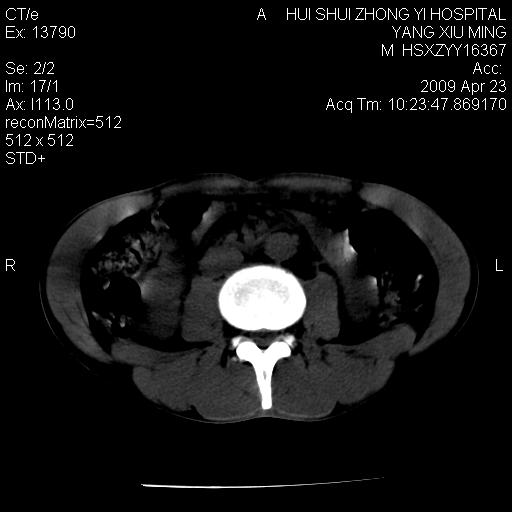

上腹部疼痛一月,呕吐10天,发现左侧颈部包快10天 胸部cr片未见明显异常。

腹膜后淋巴结增大,转移、淋巴瘤?胰腺增大,胰腺炎?占位?颈部考虑增大淋巴结。建议腹部增强扫描。

缺少强化资料,暂考虑胰腺癌广泛转移.

连最基本的ct值都没有测        腹部的窗宽窗位太大了     影响诊断

黑!广泛淋巴结肿大不符合胰腺癌转移。胰腺周围淋巴结肿大致使胰腺看起来大。考虑淋巴瘤可能大。